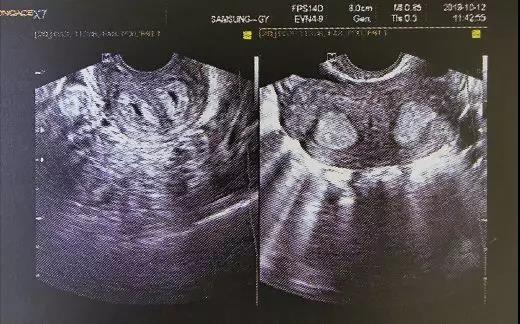

(小杨B超报告图)

小杨,是上个月,我院业务副院长-妇产科冷艳主任医师收治的一位纵隔子宫患者,今年21岁,未婚有同居男友。

小杨的情况属于子宫完全纵隔、阴道完全纵隔、双宫颈,右侧卵巢还有5cm左右大小畸胎瘤。